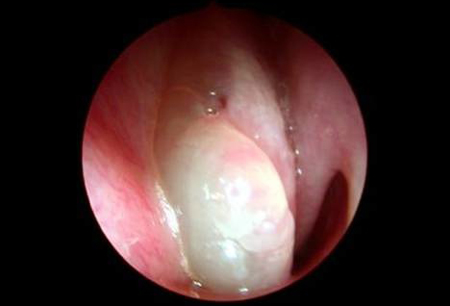

Nasal polyps can be a part of this condition. Learn vocabulary, terms and more with flashcards, games and other study tools. Do you have strange bumps inside your nose? These polyps vary in size, and they can grow singly or in clusters. Sinonasal polyposis refers to the presence of multiple benign polyps in the nasal cavity and paranasal sinuses. Nasal polyps are painless soft growths inside your nose. It is rather important to classify and stage nasal polyposis in order to decide the magnitude of the disease and to decide on the optimal management modality. Nasal polyps grow in inflamed tissue of the nasal mucosa. Natural auroh's patented homeopathic treatment. The type of anaesthetic might depend on the. They hang down like teardrops or grapes. Polypoid polyps look like a mushroom, but flop around inside the intestine because they are attached to the lining of the colon by a thin stalk. Overview chronic rhinosinusitis (crs) is one of the most common medical conditions worldwide, reported to affect almost 12% of the conditions associated with nasal polyps crswnp is often associated with other medical conditions. Nasal polyps are soft, painless, noncancerous growths on the lining of your nasal passages or sinuses. They line the inside of your nose or your sinuses. They may grow larger, however, and may need to be. They usually occur in both the right and left nasal there are two types of nasal polyps, antrochoanal polyps and ethmoidal polyps. They are divided into two main types: A nasal polyp is a benign (noncancerous) tumor that grows from the lining of the nose or sinuses. But not all people with this condition will develop nasal polyps. 19 natural treatments + healthy diet & lifestyle changes. These may be difficult to identify because they are not as prominent as polypoid or sessile polyps with the commonly available methods of diagnosing polyps. In certain situations, nasal polyps can alter the craniofacial skeleton because unremoved polyps can extend intracranially and into the orbital vaults. Nasal polyps are often related to other chronic diseases and tend to last for long periods of time. The following list of conditions have 'nasal polyps' or similar listed as a symptom in our database. Polyp formation in the nasal cavity is due to chronic allergic rhinitis, chronic sinusitis, and, less commonly due to underlying disease such as cystic fibrosis. Epidemiology it is most commonly encountered in adults and rare in children. Learn about causes, risks, home remedies, and. Antrochoanal polyps are less common and originate in the maxillary. Find out about nasal polyps, which are painless soft growths inside your nose. Nasal polyps are growths that result from inflamed mucous membranes in the sinuses and nasal passages.

Calameo Different Types Of Nasal Polyps Treatment . Nasal polyps (np) are benign swellings of the mucosal lining of the paranasal sinuses.

Nasal Polyps Pose Treatment Challenges , Broadly Defined, Nasal Polyps Are Abnormal Lesions That Originate From Any Portion Of The Nasal Mucosa Or Paranasal Sinuses.